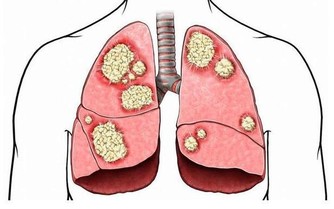

其實,尿毒症並不是一種獨立的疾病,它是各種腎病終末期腎功能衰竭而導致的一系列症狀的總稱。

原來,各種原因引起的腎臟結構和功能障礙,比如說感染、糖尿病和高血壓等疾病都可導致腎髒病變,持續三個月以上就稱為慢性腎髒病了。據調查,我國慢性腎髒病的患病率為10.8%,也就是說,有十個中國人中就有一個患有此病。

慢性腎髒病是一個長期持續進展的過程,共分為5個時期。前3個時期中,腎臟的代償作用可以基本可以完成腎臟的功能,病人通常沒什麼不舒服。而到了第4期,腎功能的損害已經進入不可逆的階段,病人的食慾減退、貧血、血鉀高、消化道出血等症狀日漸明顯,甚至心臟等其他器官也開始衰竭。

當慢性腎髒病進展到終末期,就是我們常說的“尿毒症”了。